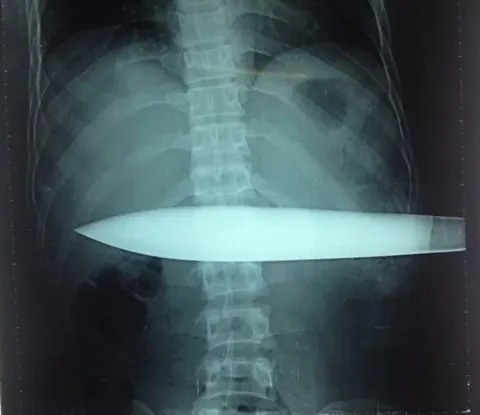

Hình ảnh X quang cho thấy con dao đâm gần hết phần bụng của nạn nhân - Ảnh: Bác sĩ cung cấp

Hình ảnh phim chụp X-quang chưa thể đánh giá hết được tổn thương vùng bụng, tuy nhiên tình trạng sức khỏe của bệnh nhân khá nguy kịch. Bệnh nhân T. ngay sau đó đã được chuyển vào phòng mổ cấp cứu để rút dao ra khỏi cơ thể.